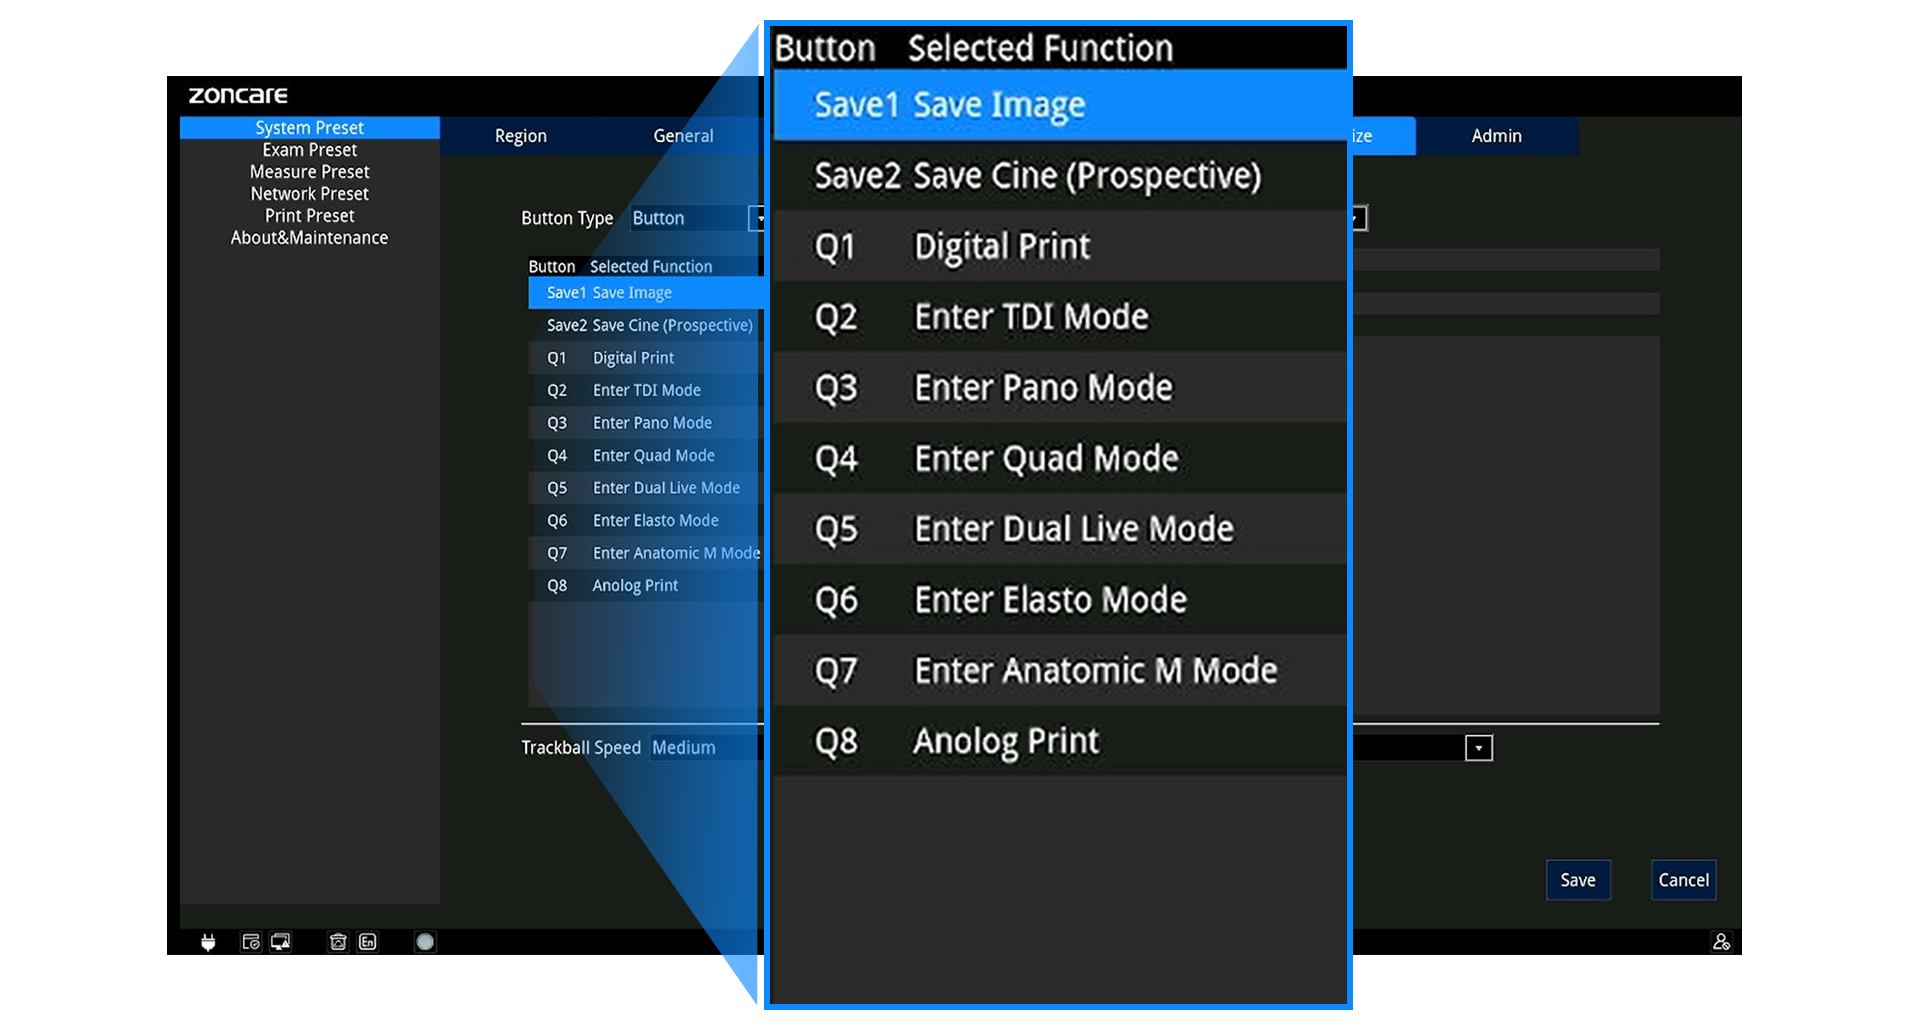

Panel ergonómico con trackball, TGC de 8 segmentos y teclas programables (Q1–Q4)

B, B-Steer, M, B/M, 2B/4B

Color Doppler (CDFI), Power Doppler (PDI/DPDI)

Doppler Pulsado (PW) y Continuo (CW)

Anatomic M (recto y curvo)

TDI (TVI, TVD, TVM, TEI)

Panorámico y Color Panorámico (EFOV)

Elastografía

3D / 4D (ZLive, Silhouette)